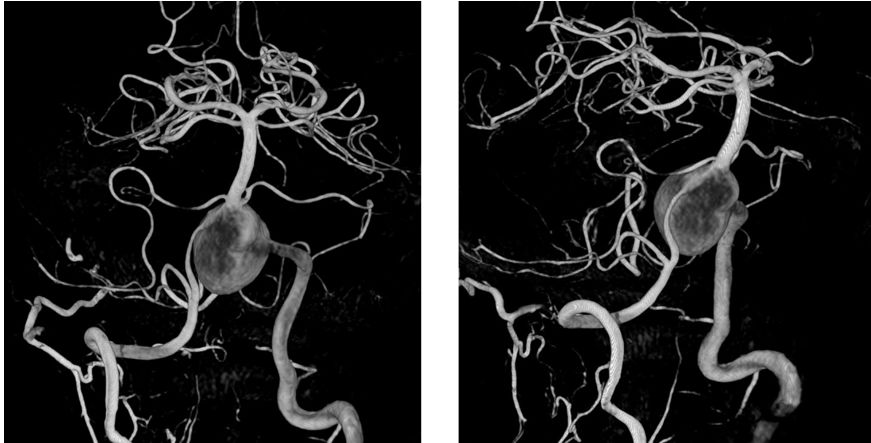

患者核磁共振显示脑桥-延髓前方流空影,考虑动脉瘤,有明显的双腔征,瘤壁有加强,且对脑干有一定的压迫。

经左椎动脉造影可见椎-基底动脉汇合部巨大动脉瘤,双侧椎动脉均有累及,以左侧椎动脉为主,右侧PICA与动脉瘤有一定距离,基底动脉稍受累及,AICA距离动脉瘤较近。